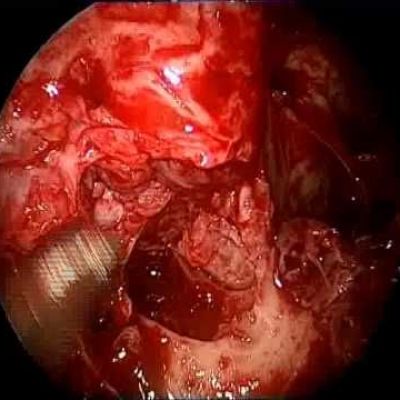

INVASIVE ASPERGILLOSIS OF SKULL BASE

Fascinating operation to remove fungal mass.